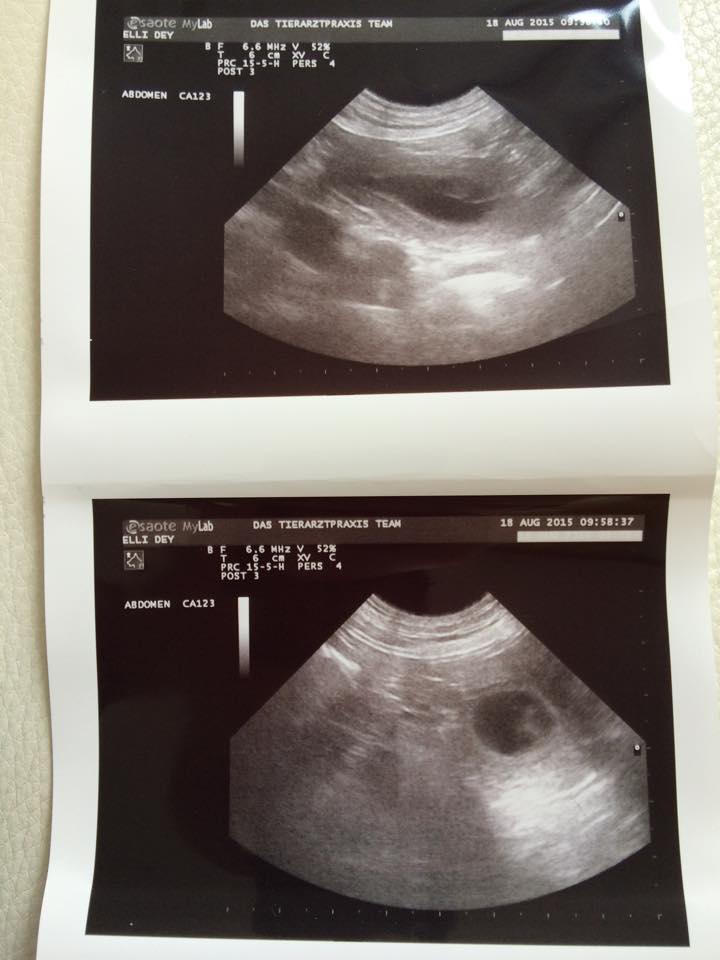

| 4. Woche | Am 22. Tag sind die Embryonen sichtbar. Der Herzschlag kann zur Diagnose der Trächtigkeit herangezogen werden. Anstrengende Aktivitäten sind jetzt zu vermeiden.Die Proteinzufuhr im Futter kann erhöht werden. Hierfür eignet sich sehr gut die Gabe von Welpenfutter. Zu diesem Zeitpunkt kann mit einer Ultraschalluntersuchung der Zustand der Trächtigkeit festgestellt werden. Besprechen Sie mögliche Risiken einer solchen Untersuchung mit dem Tierarzt. |

| Mi, 19.08.2015 bis So, 23.08.2015 | Dies ist der beste Zeitpunkt, um die Trächtigkeit anhand des Herzschlags zu diagnostizieren. Die Embroynen sind etwas walnussgroß und sind gleichmäßig im Uterus verteilt. |

Wir freuen uns riesig über den positiven Ultraschall unserer Zaubermaus und sind sehr gespannt wieviele kleine Fleckenzwerge Ende September in unserer Wurfkiste landen werden.